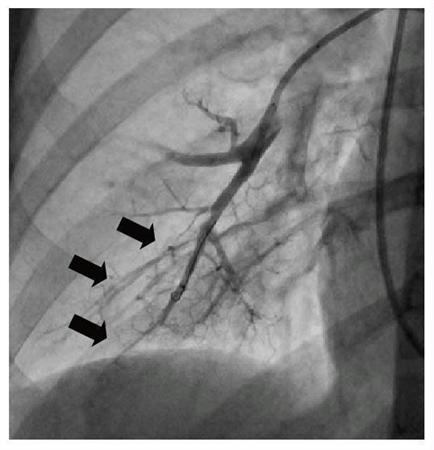

治療前、古い血栓で閉塞した肺動脈の末梢血管(国立循環器病研究センター提供)【拡大】